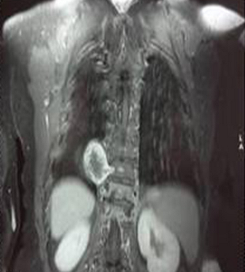

Une maladie peut cacher une autre : un mal de Pott révélant un schwannome

Hajer Ben Brahim, Wafa Chebbi

PAMJ. 2014; 19: 91. Published 26 September 2014